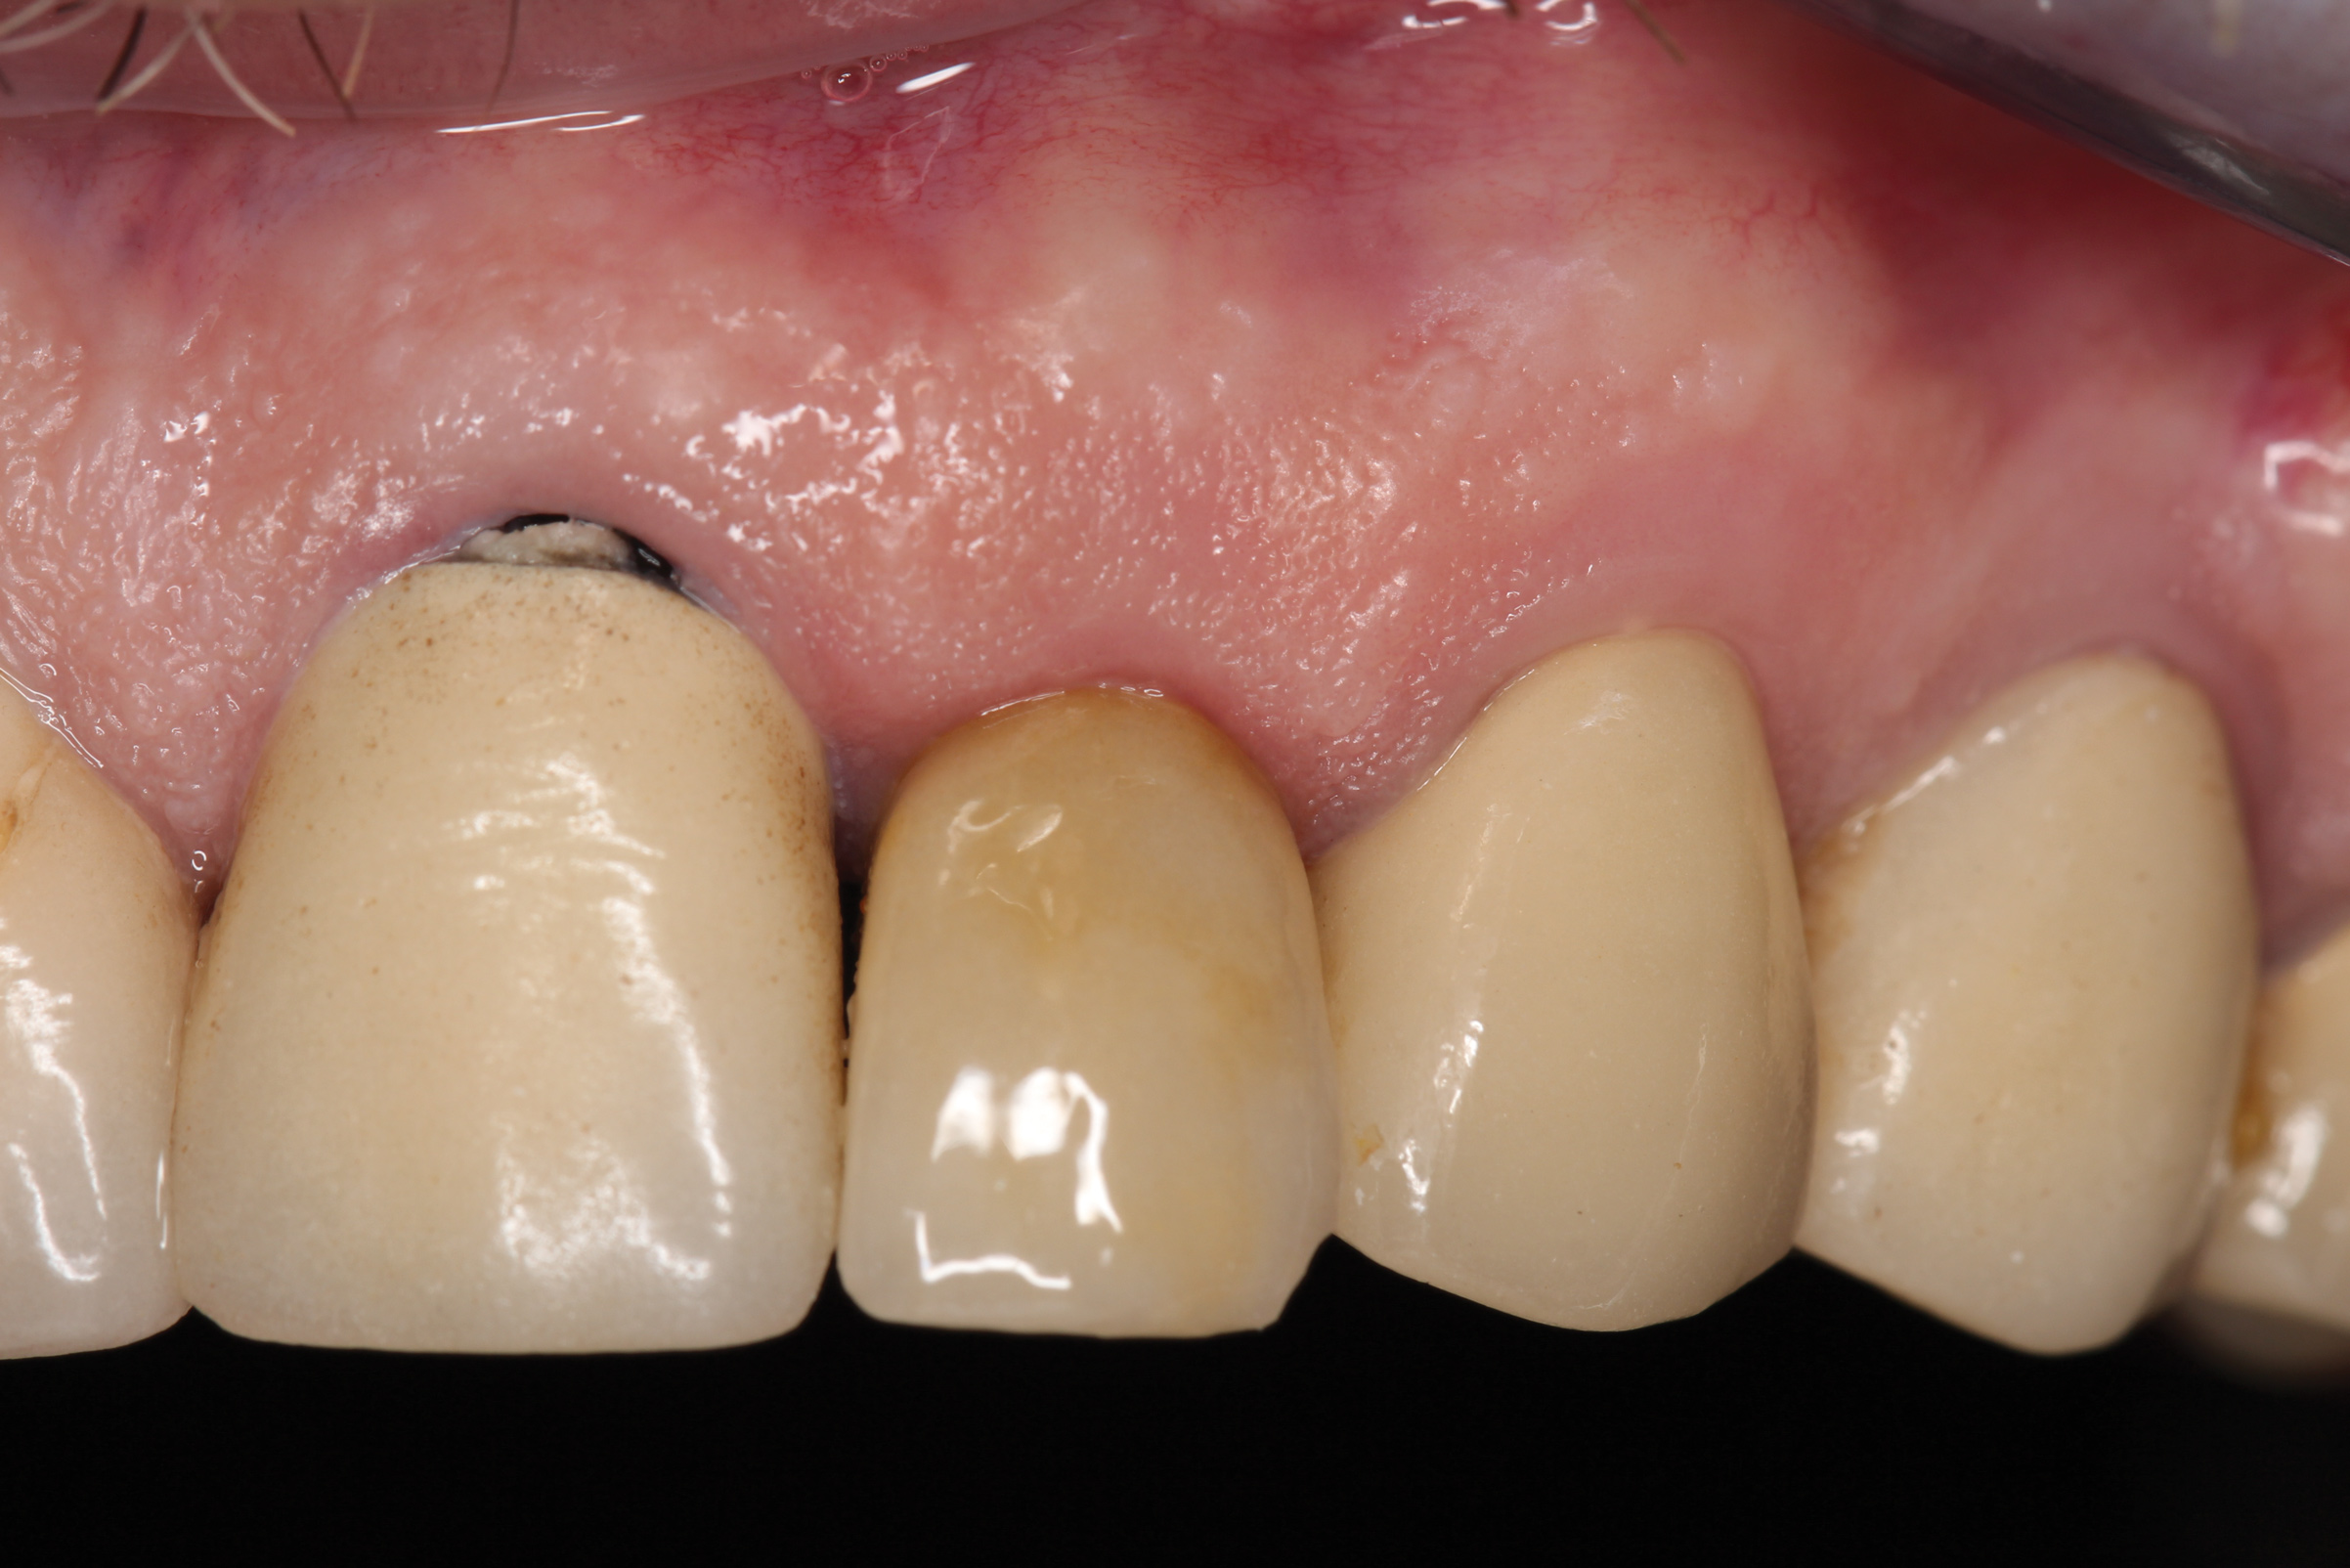

Fig 22. Final restoration after 1.5 years. Note the soft-tissue contour on the buccal aspect.

Figure 22